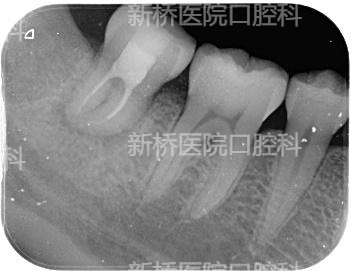

自体牙移植(auto transplantation , ATT) : 自体牙移植是将牙从一个位置移植到同一个体的另一位置,包括将埋伏、阻生、或萌出牙转移到其他缺牙部位牙槽窝内或手术制备的牙槽窝内。

本例采用3D数字化打印技术,术前模拟牙槽窝修整部位,术中用3D打印等比树脂牙试植,做到精准高效制备植入窝,减少供牙离体时间,减少供牙反复植入次数,极大减少供牙牙周膜损伤。